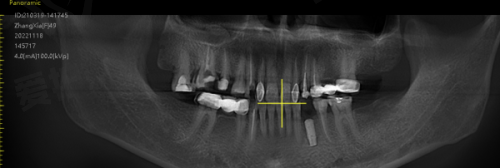

术前检查:患者来到广州曙光美云口腔后,首先会进行全方面的口腔检查。医生会通过口腔CT等设备,详细了解患者的牙槽骨情况、牙齿缺失情况以及口腔健康状况。同时,还会询问患者的病史、过敏史等信息,为制定种植方案提供依据。